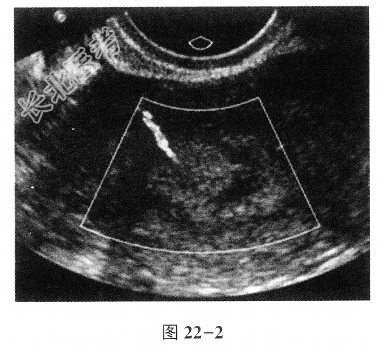

- 单项选择题患者女,36岁, 不规则阴道流血半年余,其子宫超声声像图如图22-1, 图22-2。最可能的诊断是

A、子宫内膜癌

B、子宫内膜息肉

C、子宫绒毛膜癌

D、子宫黏膜下肌瘤

E、子宫内膜不典型增生